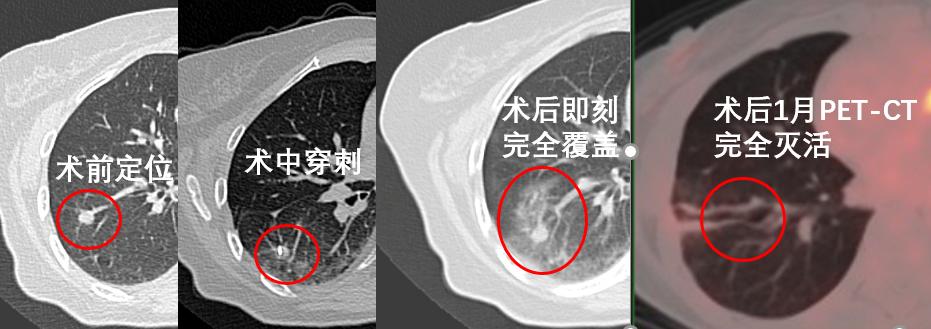

CT扫描确定肺转移病灶,定位穿刺点后局麻,导航仪引导将一根直径仅2mm的微波针穿刺进入肺转移瘤,启动消融机器,局部快速升温至100℃以上,消融至预设时间后CT扫描评估消融范围,当消融范围完全覆盖肿瘤后拔除消融针。术后伤口跟输液穿刺后伤口大小一样,没有切口和缝针,术后第二天可以下床活动,出院。